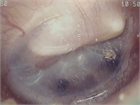

1. 耳閉感を伴う疾患は様々で、患者の訴えも「耳がつまる」以外に「耳がふさがった感じ」「耳の違和感」「音が反響する」「水が入ったような」など多様であるため、初診時の丁寧な問診が重要である(推奨度1)

1. 異物など除去により症状が消失するケースを除き、聴覚検査は診断に必須である(推奨度1)

1. 耳閉感を訴えている症例の中には、耳以外の疾患が原因の場合がある。特に脳血管疾患、腫瘍性疾患など生命予後を左右する鑑別疾患の可能性を想定した場合には、積極的に画像検査を施行する(推奨度1)